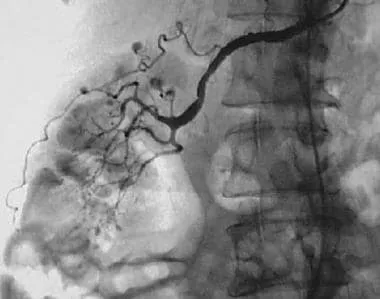

- Presents with fever, myalgia, abdominal pain; "rosary sign" on angiography (aneurysms).

- Angiography reveals multiple aneurysms and stenoses.

⭐ High-Yield: PAN characteristically spares the pulmonary arteries. The "beads on a string" appearance on renal or mesenteric angiography is a classic finding.

- PAN: Angiography reveals microaneurysms and stenoses in renal, mesenteric, or hepatic arteries ("rosary sign" or "beads-on-a-string"). A key alternative when biopsy is inaccessible.